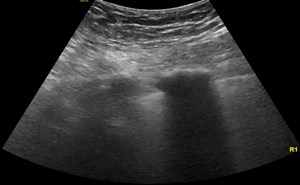

69-year old male with history of hypertension, diabetes, squamous cell carcinoma of larynx status post chemotherapy, radiation, total laryngectomy, tracheostomy dependence, and status post renal trans...